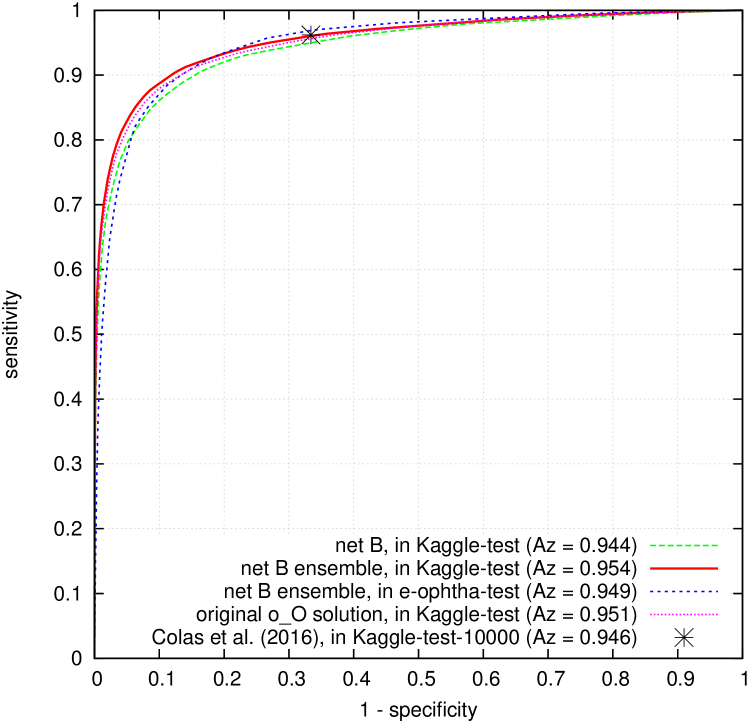

Random forest parameters, the number of trees and the maximum depth of each tree , were optimized by 5-fold cross-validation in Kaggle-train and e-ophtha-train: in Kaggle DR dataset and in e-ophtha, in both datasets. ROC curves in Kaggle-test and e-ophtha-test are reported in Fig. 8 for ‘net B’. Areas under the ROC curves for all three ConvNets are summarized in Table 4. It is important to notice that using such an ensemble of ConvNets does not necessarily turn the solution into a black box. Indeed, the heatmaps associated with the above ConvNets all have the same size. So, to support decision for a given patient, the heatmaps associated with all the networks involved in the decision process can be blended (one blended heatmap per eye). Furthermore, each heatmap can be weighted by the importance of the associated ConvNet in the decision process.

Performance at the image level is also very high, which was to be expected since we used efficient ConvNets from a recent machine learning competition as starting points: a performance of was achieved in Kaggle-test by the proposed framework using ‘net B’ (95 % confidence interval with DeLong et al. (1988)’s method: ). In particular, the proposed solution outperforms the system by Colas et al. (2016) (). This good performance derives in part from the above observations at the pixel level, which explains that the proposed solution also outperforms our main baseline solution, namely o_O (). The performance of the ensemble was also very high in e-ophtha-test: (95 % confidence interval: ), as opposed to for our previous solution, based in part on multiple-instance learning (Quellec et al., 2016c). The proposed ensemble strategy was extended to multiple network structures, but it did not increase performance significantly (see Table 4): because it increases complexity for a very limited benefit, we do not recommend it. It should be noted that Gulshan et al. (2016) recently reported higher performance (up to ) in smaller datasets (less than 5,000 patients) with a much better ground truth (seven or eight grades per image, as opposed to one in this study); that system does not provide pixel-level information. Abràmoff et al. (2016) also reported higher performance () in a smaller dataset (874 patients) with a better ground truth (three grades per image) for a system relying on pixel-level information for training.